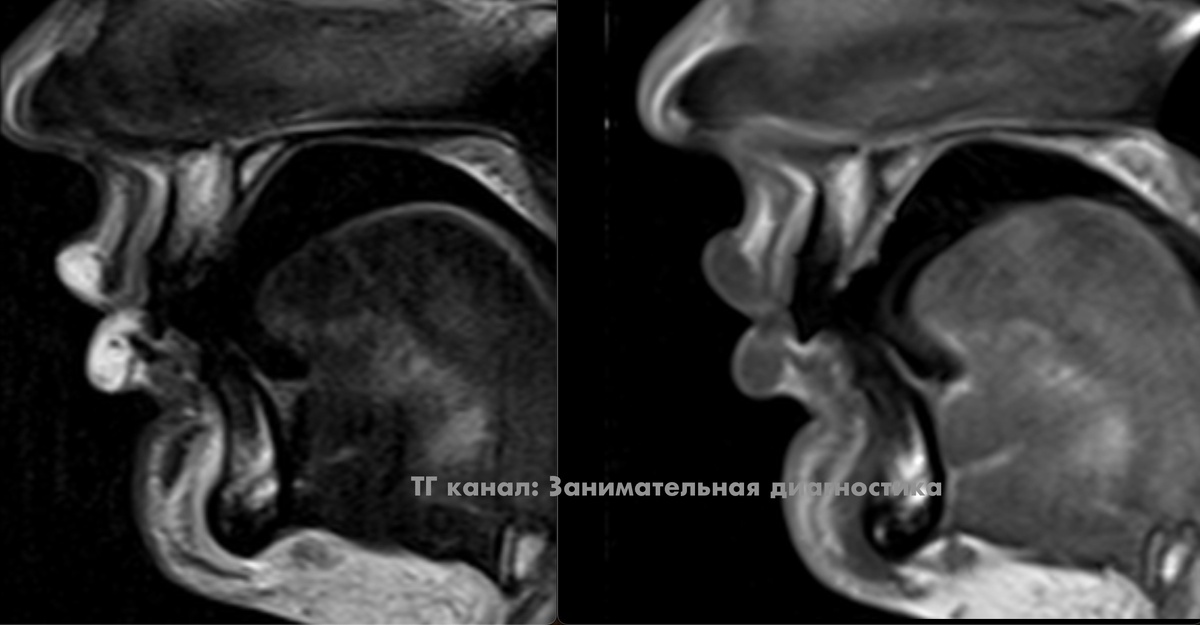

Каких нибудь 20 лет назад доктор, анализируя МРТ, мог бы впасть в ступор, пытаясь понять что такое с губами. Но мы то в наше время живём и понимаем - это просто молодая особа сделала в губы инъекции филлера (гиалуроновой кислоты). Красота! Коллега предположил, что такими губами, наверное, хорошо играть на губной гармошке. P.S. тёмные линии в толще губ на боковых срезах - это мышцы. Также хорошо видно зубы. *** Читать ещё на Дзен:

Каких нибудь 20 лет назад доктор, анализируя МРТ, мог бы впасть в ступор, пытаясь понять что такое с губами.

Но мы то в наше время живём и понимаем - это просто молодая особа сделала в губы инъекции филлера (гиалуроновой кислоты).

P.S. тёмные линии в толще губ на боковых срезах - это мышцы. Также хорошо видно зубы.